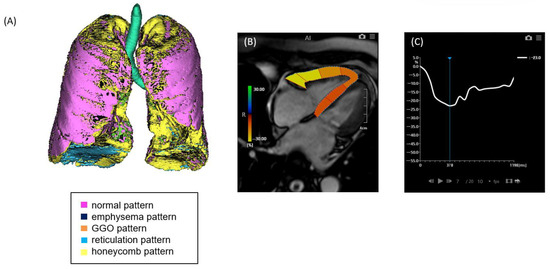

Figure 2. A case of ILD with advanced pulmonary fibrosis and impaired right ventricular (RV) strain. (A) Quantitative CT-based 3D reconstruction of lung parenchymal patterns. Normal lung parenchyma (pink), emphysema (dark blue), ground-glass opacity (GGO, orange), reticulation (light blue), and honeycombing (yellow) are segmented, with extensive honeycombing and emphysema observed. (B) Cardiac MRI showing RV strain analysis with feature tracking, indicating reduced myocardial deformation predominantly in the free wall. (C) Strain–time curve of the right ventricle showing severely reduced peak longitudinal strain (−7.6%).

2.2. CT Image Acquisition and Analysis

Non-contrast chest computed tomography (CT) scans were obtained during full inspiration in the supine position using multidetector CT scanners (Aquilion 64, Aquilion ONE 320, or Aquilion Precision 160; Canon Medical Systems, Japan). The slice thickness was 0.5 or 1.0 mm. The median interval between CT and RHC was 71 days (mean, 88.5 days; range, 0–325 days). CT data were analyzed using the GHNC system, which classifies lung parenchyma into six categories—normal (N), emphysema (E), ground-glass opacity (GGO, G), consolidation (C), reticulation (R), and honeycombing (H)—based on local histogram features and CT attenuation values [9,10]. These categories were predefined using datasets from healthy individuals and patients not included in the current study. The system automatically calculated the volume of each category and the total CT lung volume (CTLV), displaying the results as color-coded overlays. Volumetric data for each category were expressed as percentages of the CTLV. The diseased lung area was defined as the sum of all non-normal parenchymal patterns, including GGO, honeycombing, reticulation, emphysema, and consolidation (Figure 1 and Figure 2). In this study, the extent of fibrosis was quantitatively assessed using the percentage of diseased lung area—defined as the sum of GGO, reticulation, honeycombing, consolidation, and emphysema—relative to the total CT lung volume (i.e., expressed as a percentage of the entire lung). This quantitative measure was used as a surrogate marker for the stage of pulmonary fibrosis.